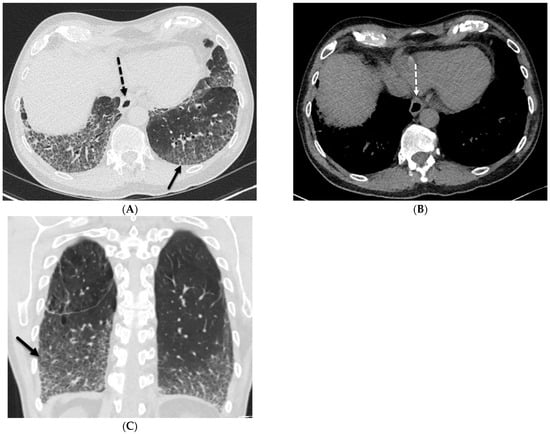

Smooth![]() | Infectious: Viral pneumonia including COVID-19 pneumonia, Pneumocystis jiroveci pneumonia (PJP) Miscellaneous: Pulmonary edema, pulmonary hemorrhage Inherited: Yellow nail syndrome (YNS), pulmonary capillary hemangiomatosis (PCH), pulmonary veno-occlusive disease (PVOD), pulmonary lymphangiomatosis, coatomer subunit alpha (COPA) syndrome Depositional: Pulmonary alveolar proteinosis (PAP) Iatrogenic: Drug toxicity, radiation pneumonitis, lipoid pneumonia, e-cigarette or vaping use-associated lung injury (EVALI) Granulomatous: Erdheim Chester disease (ECD) |

Nodular![]() | Neoplasia: Leukemia, lymphoma, Kaposi’s sarcoma, lymphangitic carcinomatosis Interstitial lung diseases: Nonspecific interstitial pneumonia (NSIP), usual interstitial pneumonia (UIP), lymphoid interstitial pneumonia (LIP) Exposures: Silicosis, coal worker’s pneumoconiosis (CWP), asbestosis Inherited: Chronic granulomatous disease, Niemann–Pick disease Depositional: Amyloidosis Iatrogenic: Silicone embolization Granulomatous diseases: Sarcoidosis Infiltrative: IgG4-related lung disease (RLD) |

Irregular![]() | Granulomatous diseases: Sarcoidosis Interstitial lung diseases: Usual interstitial pneumonia (UIP) Inhalational: Asbestosis |